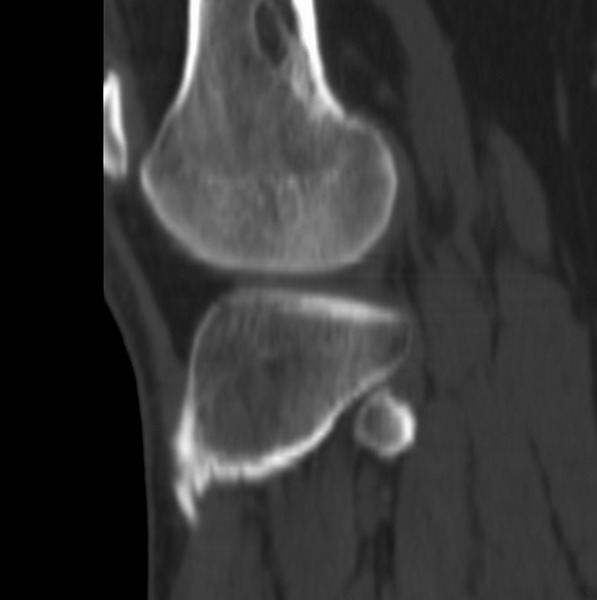

右侧膝关节疼痛一月

男、48

股骨下段、胫骨上段。

1、股骨干骺端病变考虑干骺端纤维性皮质缺损愈后(非骨化性纤维瘤)改变,胫骨近端内生骨瘤(或干骺端纤维性皮质缺损愈后改变);

2、骨关节炎,骨质增生,股骨外侧髁退变性囊肿(关节面软骨下囊肿);

1、股骨干骺端病变考虑干骺端纤维性皮质缺损愈后(非骨化性纤维瘤)改变,胫骨近端内生骨瘤;